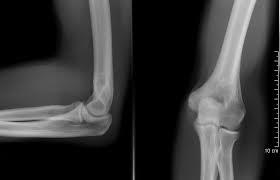

2. TROCLEAR

• Segmento Polea

1. Las superficies articulares son una polea o tróclea y dos carillas separadas por una cresta. Ejecutan los movimientos de flexión y extensión. Por ejemplo, la articulación del codo.

Annotations:

• Presenta movimientos de. -Flexión -Extensión